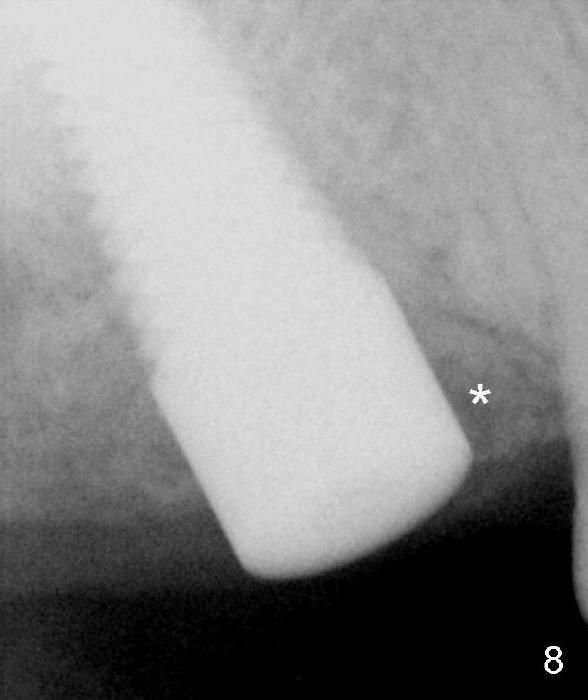

Fig.8 is taken 8 months postop. Both mesial (*) and distal gaps have apparently closed probably due to bone graft and regeneration. Difficulty is encountered when the implant is restored. It was placed too high. There is biologic width issue mesially.